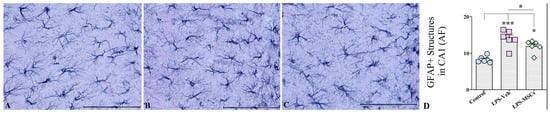

2.8. MSC Treatment Attenuates LPS-Induced Astrocytic Hyperplasia and Hypertrophy